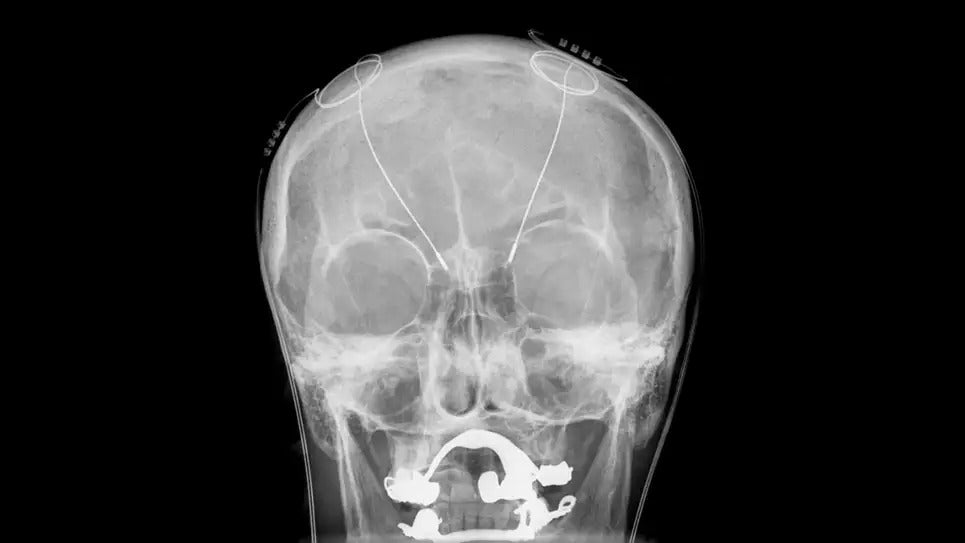

5 tratamientos médicos reales que suenan a ciencia ficción

Los órganos de cerdo humanizados y los implantes cerebrales que mejoran el estado de ánimo son algunas de las innovaciones médicas más futuristas de los últimos años.

La medicina moderna ha extendido nuestras vidas y reducido el sufrimiento en todo tipo de formas. Muchas de las intervenciones impactantes que tenemos disponibles hoy han sido Durante mucho tiempo, como los antibióticos, la mayoría de los analgésicos y diversas formas de detección del cáncer. Pero de vez en cuando, los científicos idear tratamientos novedosos que salten la línea de “cool” a “whoa”. Aquí hay cinco innovaciones médicas de ciencia ficción que ya aquí o cerca de cumplimiento.